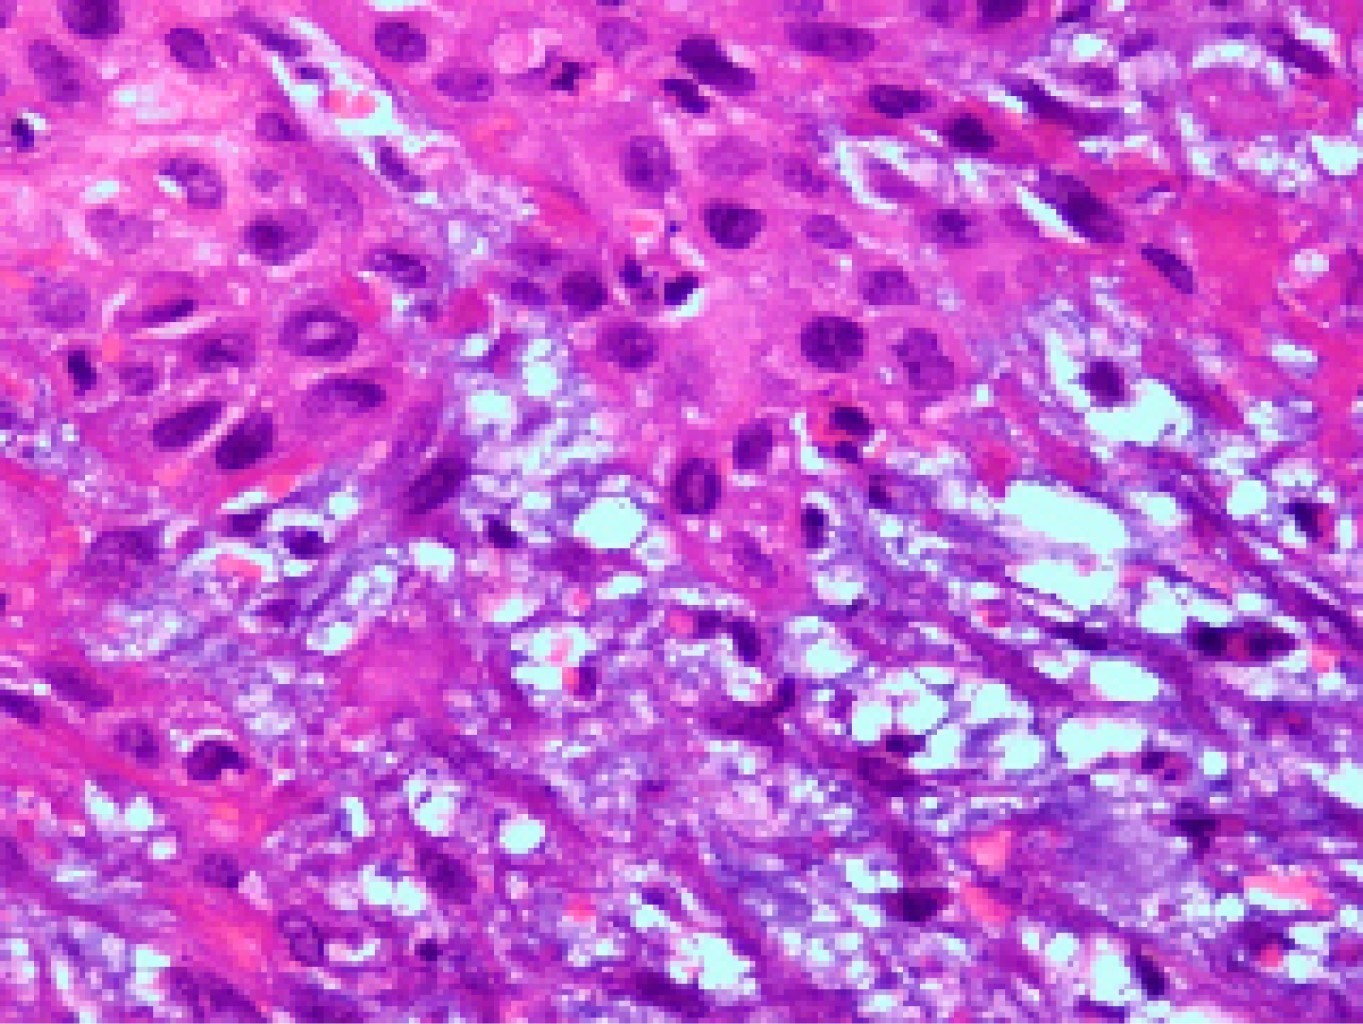

Given the disparity results of the imaging studies, an excisional biopsy of the plantar lesion was performed. Intraoperatively, it was shown that the invasion of deep layers would make it unfeasible to get a peritumoral wide margin free of tumor. The pathological study revealed the existence of a well-differentiated keratinizing squamous carcinoma, ulcerated and infiltrative, invading the surgical margins (Figures 2, 3 and 4). The microbiological study of the intraoperative samples various bacteria were isolated: Proteus mirabilis, Corynebacterium sp. and S. aureus.

The pathological diagnosis can be difficult since the lesion appears to be a common wart, therefore a deep biopsy is necessary6 since the differential diagnosis is made by the malignant invasive proliferation of the dermis by the carcinoma.5